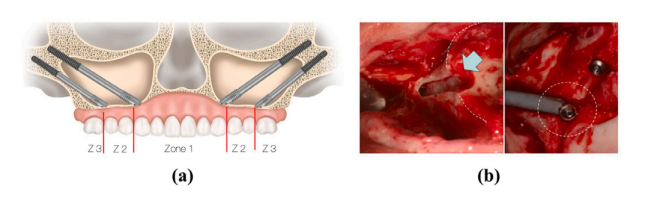

Fig. 1. (a) and (b) depict the virtual and actual schematics of zygomatic implantation,respectively (Bedrossian et al., 2023).

图1:(a)和(b)分别描绘了颧骨种植的虚拟示意图和实际示意图(贝德罗斯ian等人,2023年)。

1.1 研究背景 颧骨种植手术是严重上颌骨萎缩患者口腔修复的一种重要治疗选择,它能够避免过度创伤和漫长的骨移植手术流程(阿帕里西奥等人,2014年;罗森施泰因,2020年)。如图1所示,在手术过程中,外科医生通常会将颧骨种植体穿过上颌骨底部植入颧骨,以便进行后续治疗(赫查诺维奇等人,2016年)。具体来说,如果患者图1中的1区、2区和3区出现萎缩,那么在颧骨的每一侧会植入两颗颧骨种植体,这被称为“四种植体法”(达沃和大卫,2019年)。如果只有2区或3区出现萎缩,通常在颧骨的每一侧只植入一颗颧骨种植体,这被称为“经典法”(凯默勒等人,2023年)。 然而,由于种植空间有限且解剖结构复杂,种植体植入位置的任何显著偏差都可能导致继发性创伤或种植体松动,这给牙科临床医生带来了挑战,尤其是在采用“四种植体法”时(鲁埃达和卡塔兰,2023年)。 作为有效缓解上述困境的一种手段,计算机辅助手术技术在颧骨种植手术中得到了广泛应用。其中,手术导航与机器人技术的结合是众多学者关注的领域(陶等人,2022年;吴等人,2022年;拉梅赞扎德等人,2021年;巴莱罗等人,2023年b;范等人,2024年;奥利韦托等人,2023年;佩莱格里诺等人,2020年b;周等人,2021年;鲁埃达等人,2023年;邓等人,2023年;周,2023年)。在这种方法中,外科医生通常会在手术前根据患者的CT扫描结果预先规划种植路径。然后,在手术过程中,他们在手术导航或机器人的辅助下沿着规划好的路径进行种植,以确保达到预期的治疗效果(蓬努萨米和米洛罗,2020年;里戈等人,2021年)。目前,在导航或机器人辅助下的术中种植体植入精度已达到毫米级别(巴莱罗等人,2023年a;范等人,2023年),这也对术前规划的有效性提出了更高的标准。 然而,尽管术前规划是术中导航的重要准备工作,但颧骨种植的术前规划尚未取得重大突破,临床上大多仍依赖通过商业医疗软件进行人工设计(莫罗等人,2022年;里纳尔迪和甘兹,2019年;邢等人,2021年)。人工术前规划要求外科医生在患者的术前CT扫描图像上仔细确定种植路径的起点和终点,确保每条种植路径的终点落在颧骨内,并且路径不会穿透眼眶壁或颞窝等关键区域(艾哈迈德等人,2020年;阿帕里西奥等人,2021年)。同时,这些路径还应达到最佳治疗效果,而如何客观量化这种效果也仍然存在争议(拉马尔 - 桑切斯等人,2023年)。此外,不同外科医生规划的结果可能存在显著差异,而且人工规划无法保证获得最佳的种植轨迹。实际上,确定患者种植路径的起点取决于解剖结构。由于接受颧骨种植手术的患者通常上颌骨严重萎缩,牙槽骨大量吸收,颧骨种植体的起点通常放置在腭侧,以实现四皮质骨的稳定(洪等人,2017年)。这一操作相对容易通过人工完成,而真正的挑战在于确定终点以达到上述效果(森特内罗等人,2018年)。在我们开展这项研究之前,关于确定种植轨迹最佳终点的研究尚未取得令人满意的效果,因此这仍然是解决颧骨种植自动规划问题的主要挑战,目前许多研究也仍然更多地聚焦于此(郭等人,2023年;萨纳维亚等人,2023年;沃瑟尔曼等人,2022年;顾等人,2023年;洛鲁索等人,2021年)。因此,为了克服上述规划过程中耗时、耗力、依赖经验且可重复性差的局限性,颧骨种植的自动术前规划具有重要意义。 ### 1.2 相关研究 据我们所知,目前仍然缺乏一种自动、完整、端到端的解决方案,涵盖颧骨的分割以及颧骨种植最佳路径的生成。 就当前的技术水平而言,郭等人(2023年)引入了一种虚拟设计算法,旨在通过术前规划软件(IVSP Image)确定性能最佳的种植路径。然而,他们的方法仍然局限于“经典法”种植,并且他们的最佳轨迹仅仅是从颧骨的枚举三角形顶点中选择的,这在个性化案例中提升种植效果方面仍有很大的潜力可挖。此外,该方法没有明确说明如何添加种植约束条件,或者是否能够自动实现。规划过程仍然需要一些人工干预,即确定起点和颧骨定位,这凸显了该系统在进一步实现自动化和精确化方面的需求。其他研究仍然高度依赖人工操作(萨纳维亚等人,2023年;沃瑟尔曼等人,2022年;蓬努萨米和米洛罗,2020年)。 在子任务方面,已经有一些有见地的研究。对于颧骨的分割,陶等人(2023年a)在卷积神经网络中添加了边缘监督模块,以便更专注于颧骨的轮廓,实现了对颧骨的精确分割。森田等人(2023年)利用U型网络将面骨自动分割为包括颧骨在内的八个区域,这有助于虚拟手术规划。张等人(2023年)开发了一种无偏热图编码方法,使分割框架受益,并能够准确提取颧骨。陶等人(2023年b)提出了一个两阶段网络来检测颧骨上的标志点,在我们的研究场景中,这也能够定位有效的规划区域。然而,上述研究都基于深度学习方法。由于深度学习模型缺乏可解释性是一个普遍的局限性,因此仍需要进一步验证这些模型在不同医院数据集上的可迁移性。同时,这些基于学习的方法对硬件的计算性能也有很高的要求。 对于最佳种植路径的生成,骨 - 种植体接触(BIC)是评估种植体固定效果的关键指标,因为较大的BIC通常意味着更好的固定效果,从而使治疗成功率更高(埃林森等人,2004年;特里西等人,2015年)。因此,最大化BIC已成为许多研究的共同追求(许等人,2017年;郭等人,2023年;洛鲁索等人,2021年)。为了自动获得最佳种植路径,主要存在两个挑战,即量化BIC以及确定能使BIC最大化的路径。为了解决这个问题,顾等人(2023年)开发了一种基于三维图像配准和分割的BIC量化技术。周等人(2020年)利用生物力学分析来量化BIC与种植体负荷之间的关系。佩莱格里诺等人(2020年a)基于解剖标志点和CT扫描,考虑性别、种植体类型和轨迹之间的差异以及它们对骨结合和窦内路径的影响,评估了颧骨种植的颧骨可用性并确定了最佳轨迹。尽管上述计算机辅助手术技术提供了一些思路,但它们无法自动高效地生成最佳种植路径,在关键步骤上仍然依赖人工操作,在该领域仍有很大的进一步研究和改进空间。 ### 1.3 研究贡献 基于上述背景,本研究将提出ZygoPlanner,这是一个高效的颧骨种植术前规划框架。它能够对颧骨种植中的医学指标和临床约束进行基于图形的数学量化,且不依赖任何基于学习的方法。外科医生只需花费几秒钟在患者的三维颅骨模型上点击种植起点,ZygoPlanner就会自动高效地生成最佳种植路径。具体而言,为了克服可解释的颧骨定位这一挑战,我们基于患者颅骨的几何特征构建了一个统计多平面切割模型。利用患者颅骨近似的左右对称性,我们估计模型的对称平面,并自动提取颧骨周围的有效规划点云。为了克服生成最佳种植路径的挑战,我们首先提出了一种适用于凹面几何形状的忠实于表面的点云填充算法,以便在不破坏颧骨原始表面的情况下在规划区域内获得密集的点。然后,我们以种植中心为光源建立辐射场,并提取密集光锥内的分区背光点作为替代种植终点,以生成密集的替代路径。最后,我们以图形化的方式整合了颧骨种植中的医学概念。我们创新性地利用沿三维路径位于种植体表面层内的有效规划点云的密度,实现了医学BIC的图形化表示。基于这种表示,可以在多种约束条件下获得最佳路径。 本研究的主要贡献可总结如下: 1. 我们开发了一种无需训练的、可解释的图形化方法,利用患者三维颅骨的形状先验知识实现高效的颧骨定位; 2. 我们提出了一种适用于某些凹面几何形状的忠实于表面的点云填充算法,能够在仔细保留表面完整性的同时在颧骨内填充密集的点,有助于生成密集的替代路径; 3. 我们通过分析沿三维路径位于种植体表面层内的有效规划点云的密度,实现了医学BIC的图形化表示,从而在多种约束条件下获得最佳路径。 我们提出的ZygoPlanner框架可能是首个将颧骨定位、替代路径生成以及最佳种植路径计算无缝集成的颧骨种植规划流程,旨在减轻外科医生传统上繁琐的手术规划过程。